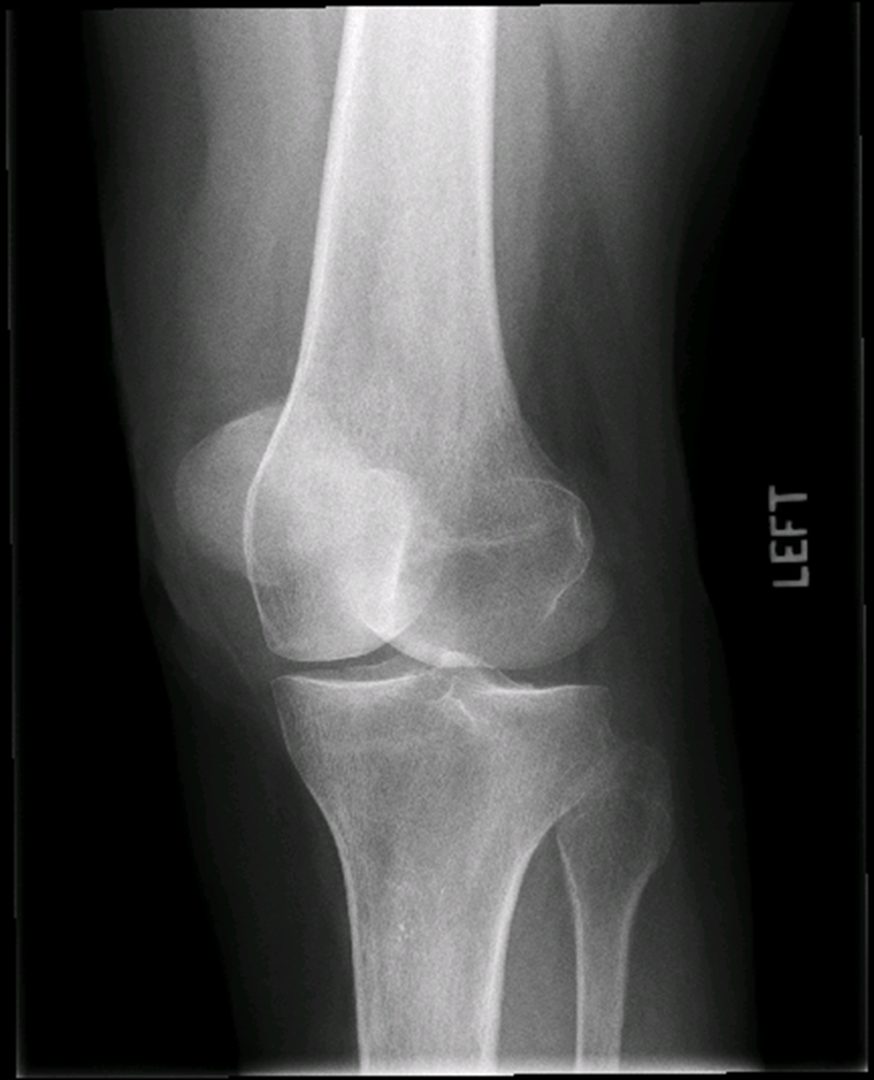

Osteoarthritis

(Degenerative Joint Disease)

Generalized disorder pathologically characterized by loss of joint cartilage and reactive new bone formation.

Cause: traumatic, stress to joints

Complications: joint pain, stiffness, trouble using joints for walking, grasping, etc

Radiographic Appearance: irregular narrowing of joint spaces and development of small bony spurs (osteophytes)

•Knee – articular ends become increasingly dense and joint narrowing is asymmetric

•Fingers – affect distal joints, marginal spurs produce well defined bony protuberances (can palpate and see knobby appearance)

•Hip – asymmetric narrowing of joint space (superiorly and laterally)

Technical: Advance Stage – Subtractive disease

•May require slight decrease

Prognosis: Some patients are unaffected by osteoarthritis while others can be severely disabled.

•Joint replacement surgery for some results in the best long-term outcome.